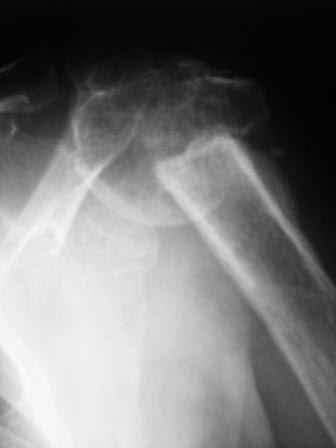

Дорогие друзья, наверное, можно обойтись здесь и без chronOS. Ведь аутокость обладает лучшими остеокондуктивными, остеоиндуктивными и остеогенными свойствами. Но мне принципиально нравится то, как ведёт себя chronOS. И, если это возможно, я всегда (или практически всегда) стараюсь потенциировать остеоиндуктивные свойства аутокости ещё и этим В3кальций фосфатом в случаях лечения ложных суставов. В прикреплённом ПДФ файле - 2 клинических случая. В первом ложный сустав локтевой кости после своеобразного остеосинтеза пластиной у молодого человека 30 лет. Выполнена декортикация, под декортиканты уложены гранулы chronOS. Остеосинтез. Активность немедленная, результат через год. По моему, В3кальций фосфат неплохо заместился костью? Второй случай посложнее и соответствует заданному Леонидом вопросу. Леонид, дабы не возвращаться снова, если Вам итересно моё мнение, то у Вашей пациентки я бы постарался выполнить нечто подобное. Немолодая (83 года) интеллигентная женщина обратилась в нашу клинику полтора года назад с несросшимся переломом и мигрировавшим фиксатором проксимального плеча. Там, где выполнили первичную фиксацию (в Москве, ясен пень) посоветовали *носить руку в кармане*, что для нормального человека, согласитесь, не всегда приемлемо. Да, здесь я выбрал PHILOS. Кстати, пишется именно так, поскольку это аббревиатура от the Proximal Humerus Internal LOcking System. Трансплантат из гребня подвздошной кости и немного гранул chronOS. А вот как и зачем здесь размещать инъекционную форму chronOS - полностью согласен с Александром Ч. - не знаю. Через год - хорошее заживление перелома при очень неплохой функции и отсутсвии боли. Имплантат решили не удалять. С уважением, Андрей Волна